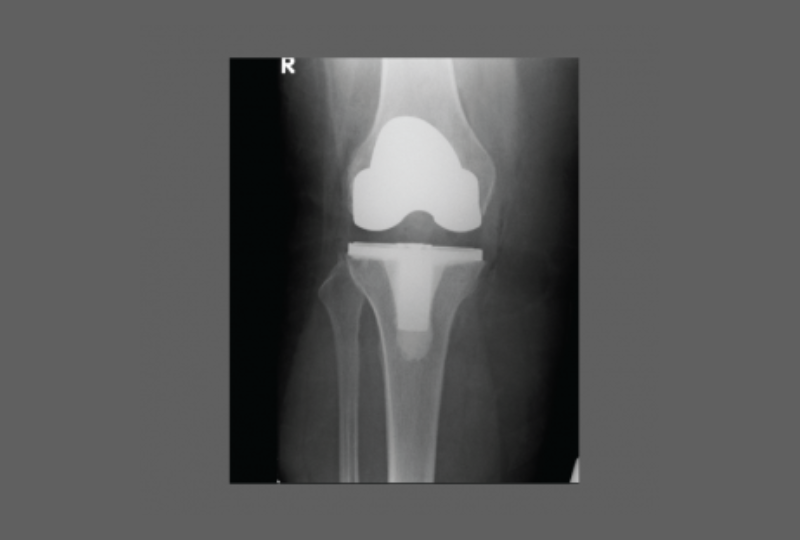

After Knee Replacement